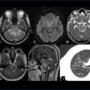

Image A & B – Axial T2 weighted images at the level midbrain and pons respectively shows ill defined T2 hypointense lesion with associated edema causing diffuse expansion of the brainstem.

Image C & D – The trace and ADC images of Diffusion weighted imaging shows patchy areas of restricted diffusion.

Image E – T2 sagittal images shows diffusion involvement of the brainstem and the hypothalamic region ( black arrow).

Image F-H : The post contrast T1MPRAGE images shows ill defined nodular enhancing lesions in random distribution in brainstem, hypothalamus and the superior vermis.

Image I : Multiple ill defined small thin walled variable shaped cysts seen distributed throughout all lobes in both lungs along with interstitial septal thickening.